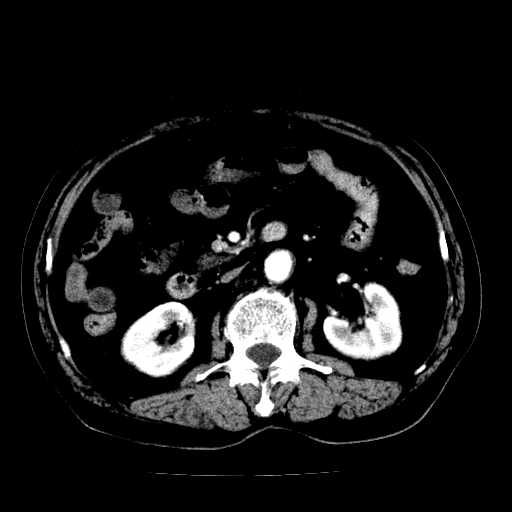

男,71岁,皮肤黄染四天。

考虑中段胆管癌

考虑胆总管癌并肝内外胆管扩张。

胰腺上端胆总管内见软组织影,强化不明显,结合临床,还是考虑低位梗阻性黄疸,胆总管癌可能性大